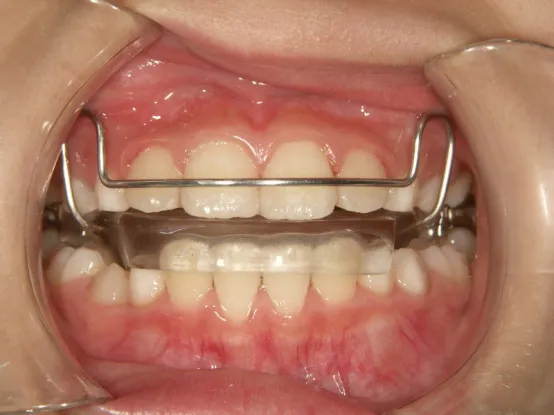

トイシャー本体

ヘッドギアー

治療中③中1:拡大・前歯の並替え、トイシャー(出っ歯を治す装置)終了

*出っ歯、過蓋咬合、口唇閉鎖不全の改善

*咬合治療用モノブロック装置(筋機能的咬合誘導装置)へ移行

*口唇閉鎖不全がなおり奇麗な口元に改善

*就寝時に使用するモノブロック装置(筋機能的咬合誘導装置)